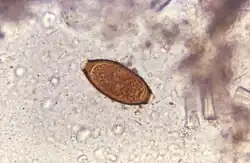

The disease usually spreads when people eat food or drink water containing these worms' eggs.[1] This may occur when contaminated vegetables are not fully cleaned or cooked.[1] Often these eggs are in the soil in areas where people defecate outside and where untreated human feces is used as fertilizer.[2] These eggs originate from the feces of infected people.[1] Young children playing in such soil and putting their hands in their mouths also become infected easily.[1] The worms live in the large bowel and are about four centimetres in length.[2] Whipworm is diagnosed by seeing the eggs when examining the stool with a microscope.[3] Eggs are barrel-shaped.[8] Trichuriasis belongs to the group of soil-transmitted helminthiases.[9]

Adult worms are usually 3–5 centimetres (1.2–2.0 in) long, with females being larger than males as is typical of nematodes. The thin, clear majority of the body (the anterior, whip-like end) is the esophagus, and it is the end that the worm threads into the mucosa of the colon. The widened, pinkish-gray region of the body is the posterior, and it is the end that contains the parasite's intestines and reproductive organs. T. trichiura eggs are prolate spheroids, the shape of the balls used in Rugby and Gridiron football. They are about 50–54 μm (0.0020–0.0021 in) long and have polar plugs (also known as refractile prominences) at each end.

A stool ova and parasites exam reveals the presence of typical whipworm eggs. Typically, the Kato-Katz thick-smear technique is used for identification of the Trichuris trichiura eggs in the stool sample. Trichuria eggs often appear larger and more swollen on Kato-Katz preparation compared to when using other techniques.[19]

Trichuriasis can be diagnosed when T. trichiura eggs are detected in stool examination. Eggs will appear barrel-shaped and unembryonated, having bipolar plugs and a smooth shell.[21] Rectal prolapse can be diagnosed easily using defecating proctogram and is one of many methods for imaging the parasitic infection. Sigmoidoscopies show characteristic white bodies of adult worms hanging from inflamed mucosa ("coconut cake rectum").[22]